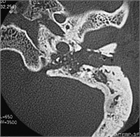

著者: 小川洋 福島県立医科大学会津医療センター 耳鼻咽喉科学講座

1. 急性限局性外耳道炎と急性乳様突起炎はどちらも外耳道が腫脹し耳介が変位することがあるが、起因菌の頻度が異なること、治療方針が異なることから鑑別が重要となる。